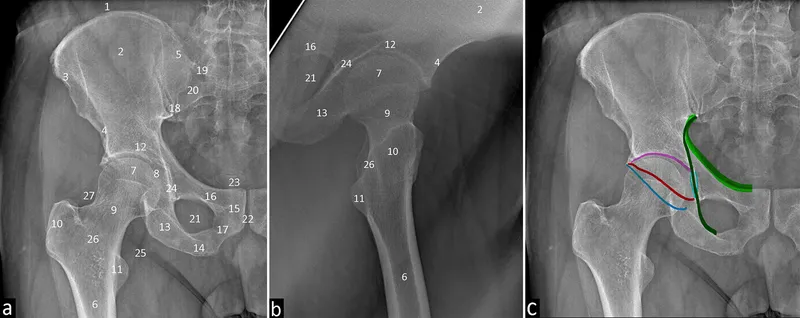

- Hip Joint:

- Landmarks: Femoral head & neck, acetabulum, greater & lesser trochanters. Shenton's line.

- Key Views: AP Pelvis, Frog-leg lateral.

- Ossification: Femoral head (4-6m), greater trochanter (2-5y).

- Key Lines: Iliopectineal, ilioischial, Shenton's line (femoral head-neck to superior pubic ramus continuity).